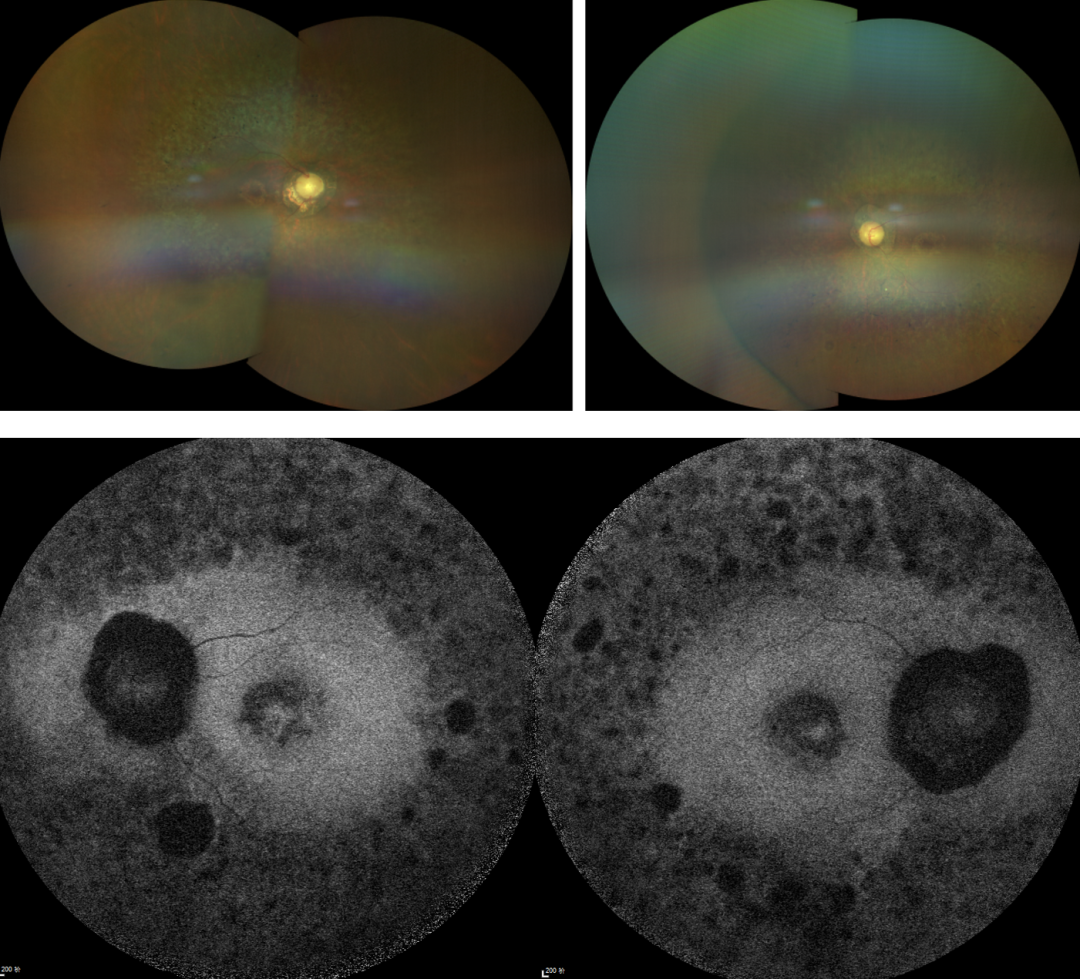

RP的診斷主要依靠眼底檢查、視野檢查、視網(wǎng)膜電圖(ERG)和基因檢測。眼底檢查可見典型的"骨細(xì)胞樣"色素沉著,ERG顯示視網(wǎng)膜功能下降,基因檢測可確定具體的突變基因。